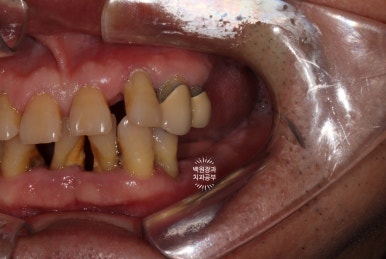

정면에서 찍어본 구강 내 사진 소견입니다.

다수의 치은연상치석, 치은연하치석이 침착되어 있고, 만성치주염으로 인해 치아가 제 위치를 상실하여,

치아의 병적이동 (pathologic migration)을 하고 있는 중이었죠.

풍치가 심해서 만성치주염을 오래 앓으신 분들은 치아 사이가 벌어져 심미적으로 불리한 모습을 많이 보이십니다.

게다가, 어금니들도 씹는 면끼리 물리지 못해서 이제 식사도 어려우신 상황이었어요.